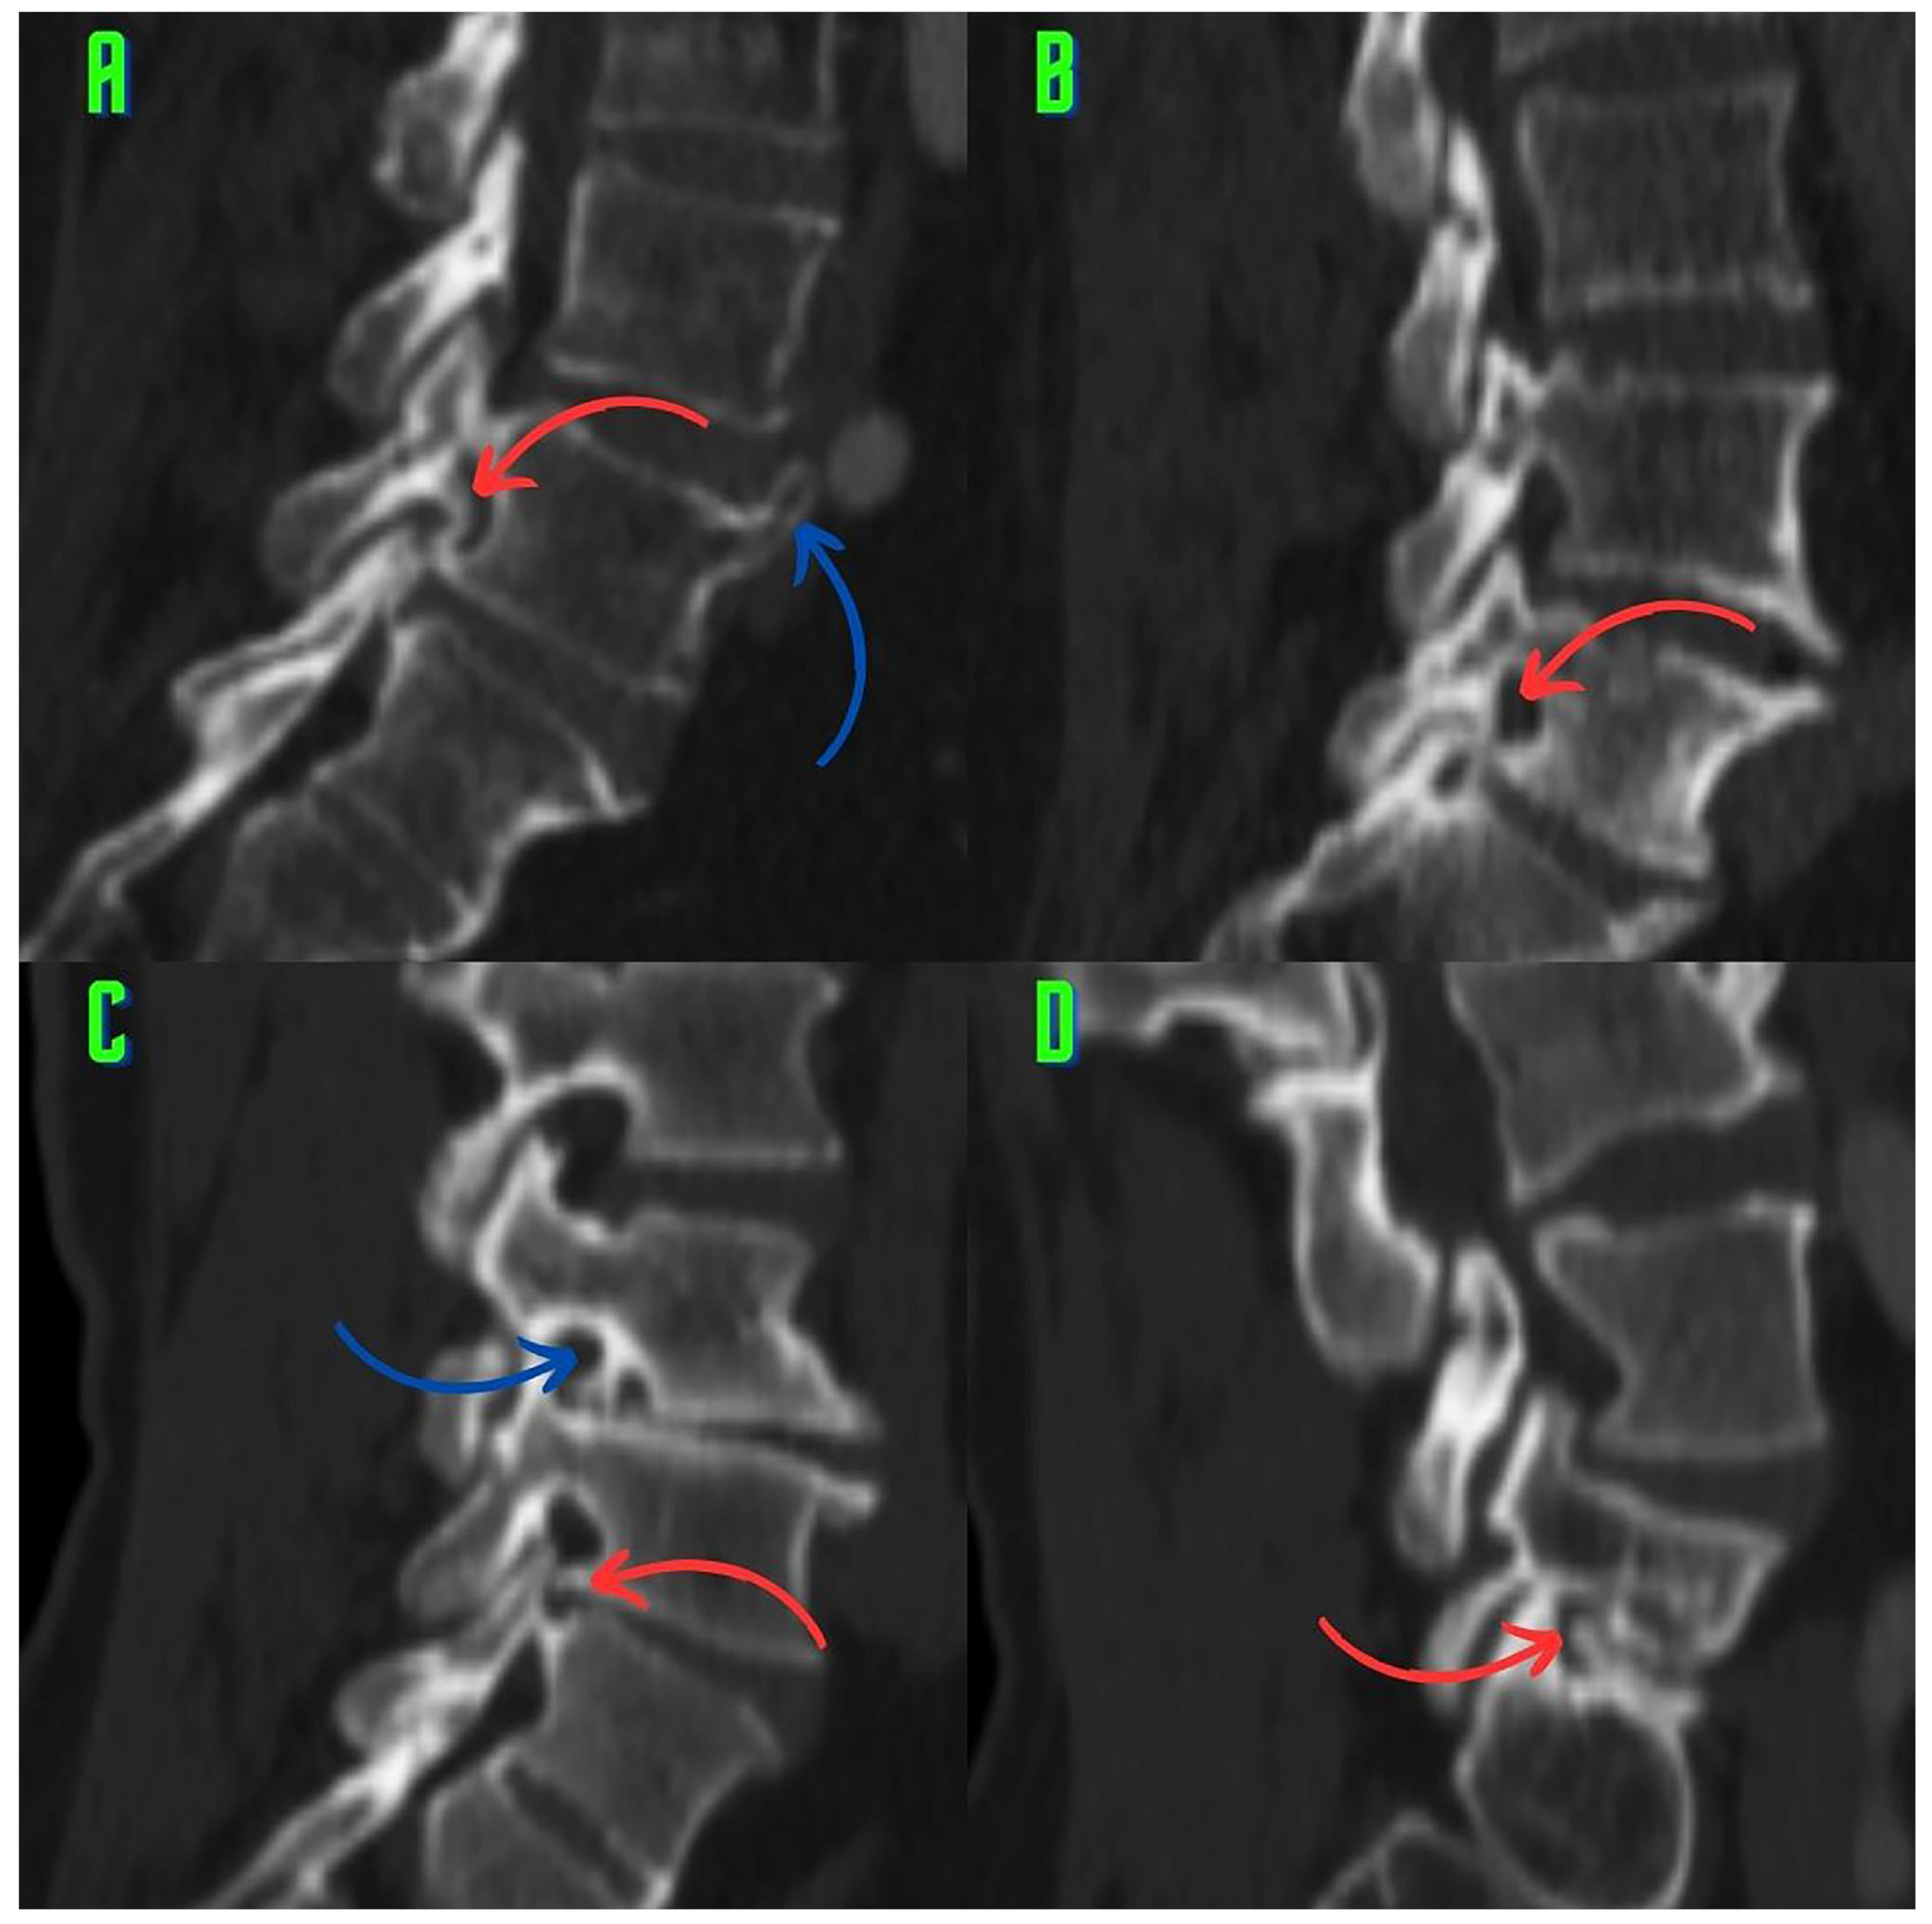

2.3. Image Analysis and Research Methods